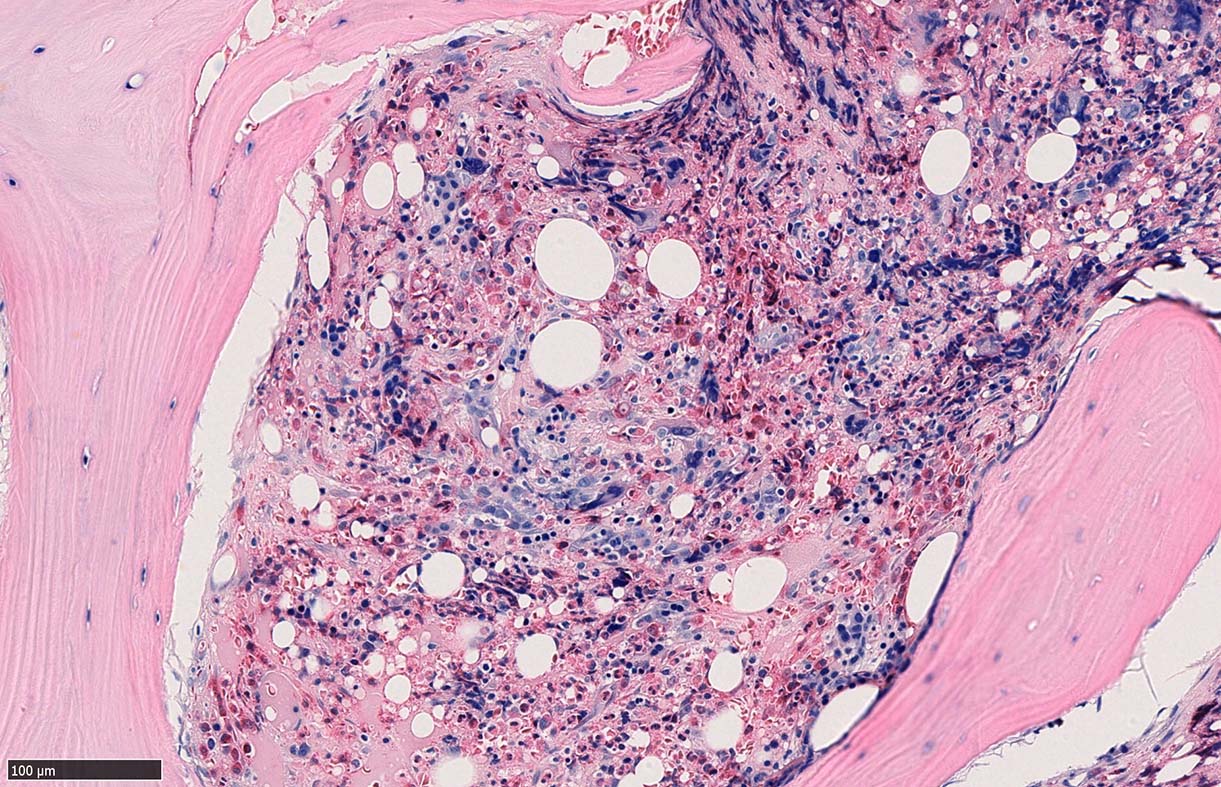

骨髄組織所見 bone marrow biopsy total 6mm in length

塗銀染色

黒染する弾性線維の増生のほか, 赤く染まる膠原線維の増生が確認される. MF-2 fibrosis. 鍍銀染色の核染色をすると膠原線維の赤染がわからなくなるので行わない.